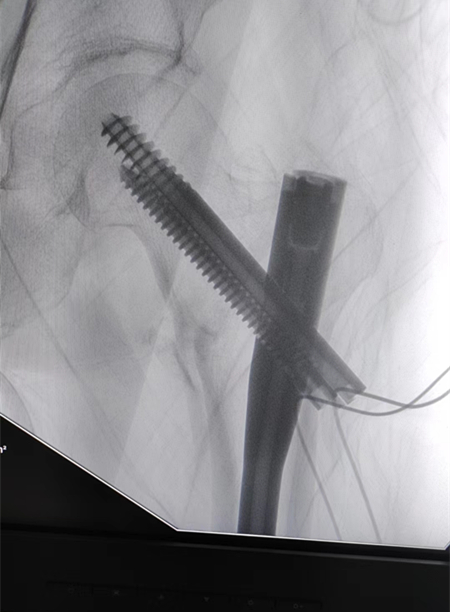

86、88、90、92、93、97、98,您以為這是一串考試成績(jī)嗎?不是,這是一個(gè)月內(nèi)我院關(guān)節(jié)外科、創(chuàng)傷骨科收治的10余名高齡患者的年齡,均為髖部骨折。通過(guò)關(guān)節(jié)外科、創(chuàng)傷骨科與麻醉科、心內(nèi)科、呼吸科、神經(jīng)內(nèi)科等兄弟科室的通力合作,均行手術(shù)治療,目前都已康復(fù)出院,戰(zhàn)勝了“人生最后一次骨折”,也獲得了患者家屬的高度贊譽(yù)。

臨床上,人生最后一次骨折,常常指的是老年人的髖關(guān)節(jié)骨折。由于骨質(zhì)疏松癥的發(fā)病率很高,根據(jù)資料統(tǒng)計(jì),男性一生中發(fā)生髖部骨折的風(fēng)險(xiǎn)高達(dá)11.2%,女性更高達(dá)23%。髖部骨折是對(duì)老年人影響最大的一類骨質(zhì)疏松骨折。不像那些發(fā)生在腕部或肩部的骨折,髖部骨折帶來(lái)的疼痛和下肢活動(dòng)障礙會(huì)迫使病人臥床,難以活動(dòng);而保守治療需要臥床三個(gè)月左右,而臥床帶來(lái)的四大并發(fā)癥,呼吸系統(tǒng)感染、泌尿系統(tǒng)感染、深靜脈血栓和褥瘡,哪一個(gè)發(fā)生了都會(huì)危及病人的生命。所以一旦發(fā)生髖部骨折,即使保守治療也會(huì)危險(xiǎn)重重,手術(shù)又有一定的風(fēng)險(xiǎn)。因此,髖部骨折在過(guò)去就被稱為“人生最后一次骨折”。手術(shù)治療可早期下地活動(dòng),但手術(shù)風(fēng)險(xiǎn)較高,存在心腦血管意外可能性較大。因此,術(shù)前需認(rèn)真進(jìn)行評(píng)估,盡可能降低手術(shù)風(fēng)險(xiǎn)。

隨著醫(yī)學(xué)技術(shù)的發(fā)展,髖部骨折手術(shù)治療已經(jīng)是比較成熟的手術(shù),高齡已不再是手術(shù)禁忌。老年人摔倒后應(yīng)積極就醫(yī),避免延誤最佳治療時(shí)機(jī)。